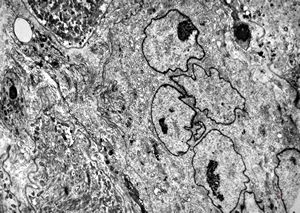

F,25y. | myopathy - atrophic and regenerating muscle cells

M,2y. | myopathy - regenerating muscle cell